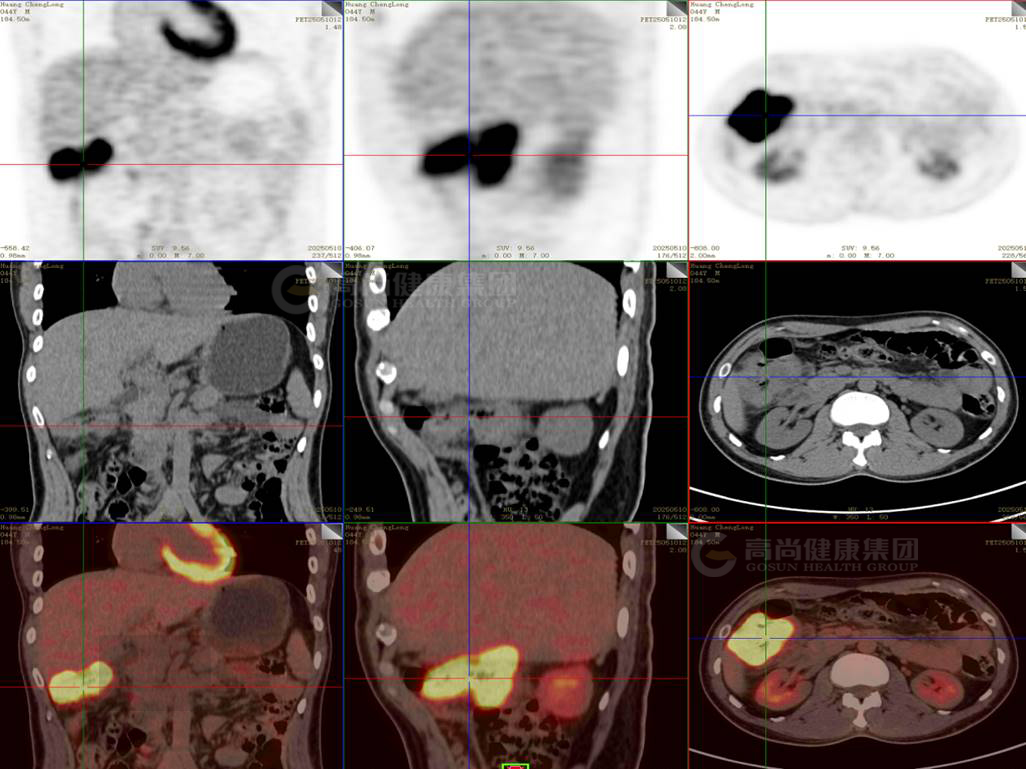

PET/CT图像

本中心PET/CT全身显像 :

升结肠见团块状放射性摄取增高影,大小约6.3cm×4.5cm×6.2cm,SUV最大值为22.6,CT于上述部位见肠壁不均匀增厚,最厚约2.3cm,浆膜层毛糙,灶周脂肪间隙模糊。

PET-CT检查结果:

升结肠团块状高代谢灶,考虑为升结肠癌,病灶侵犯肠壁全层,局部累及灶周脂肪间隙,请结合病理。